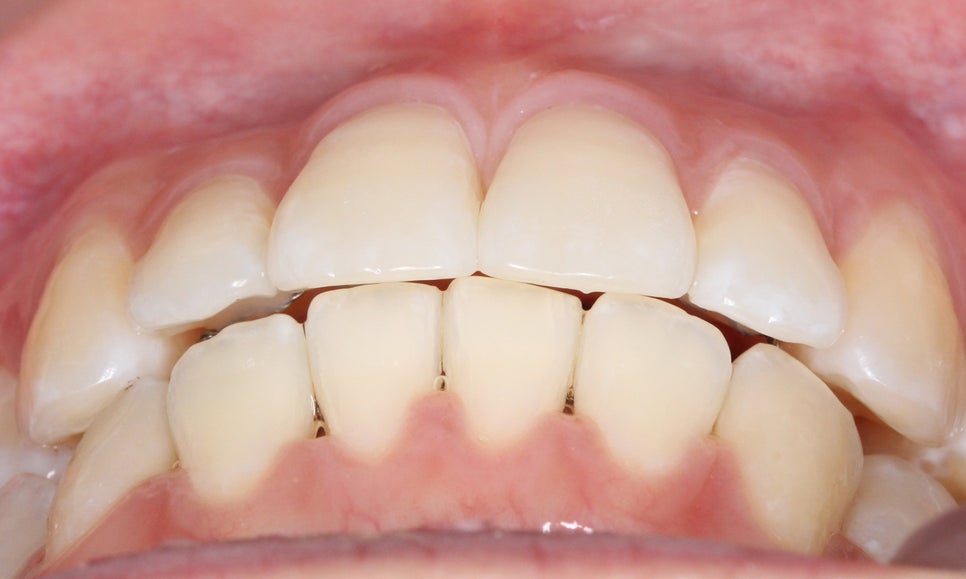

클리피씨 교정 After

2D치과

신논현치과 환자분의 클리피씨교정 후

치아의 정면 모습입니다.

교정 전 모습과 비교해보면 상하악의

중심이 바르게 잡힌 모습으로

거꾸로 교합되던 상악 측절치도

바르게 물리고 있는 것을 확인할 수 있습니다.

하악의 경우 전치부의 crowding이

사라지고 치아가 가지런하게 배열되면서

치아 사이에 블랙트라이앵글이 발생한 모습인데요,

이는 추후 레진을 올려 커버하거나 혹은

무삭제 라미네이트 '세라필름'등을 적용하여

심미성을 보완할 수 있습니다.

블랙트라이앵글의 경우 교정 전 삐뚤어짐이

심한 치아가 바르게 배열되면서 발생하거나

잇몸의 퇴축이 심해지면서 나타나게 되는데요,

블랙트라이앵글 발생 가능성이 있는 경우

교정 전 정밀진단을 통해 사전에

환자분들께 고지해 드리고 있습니다.